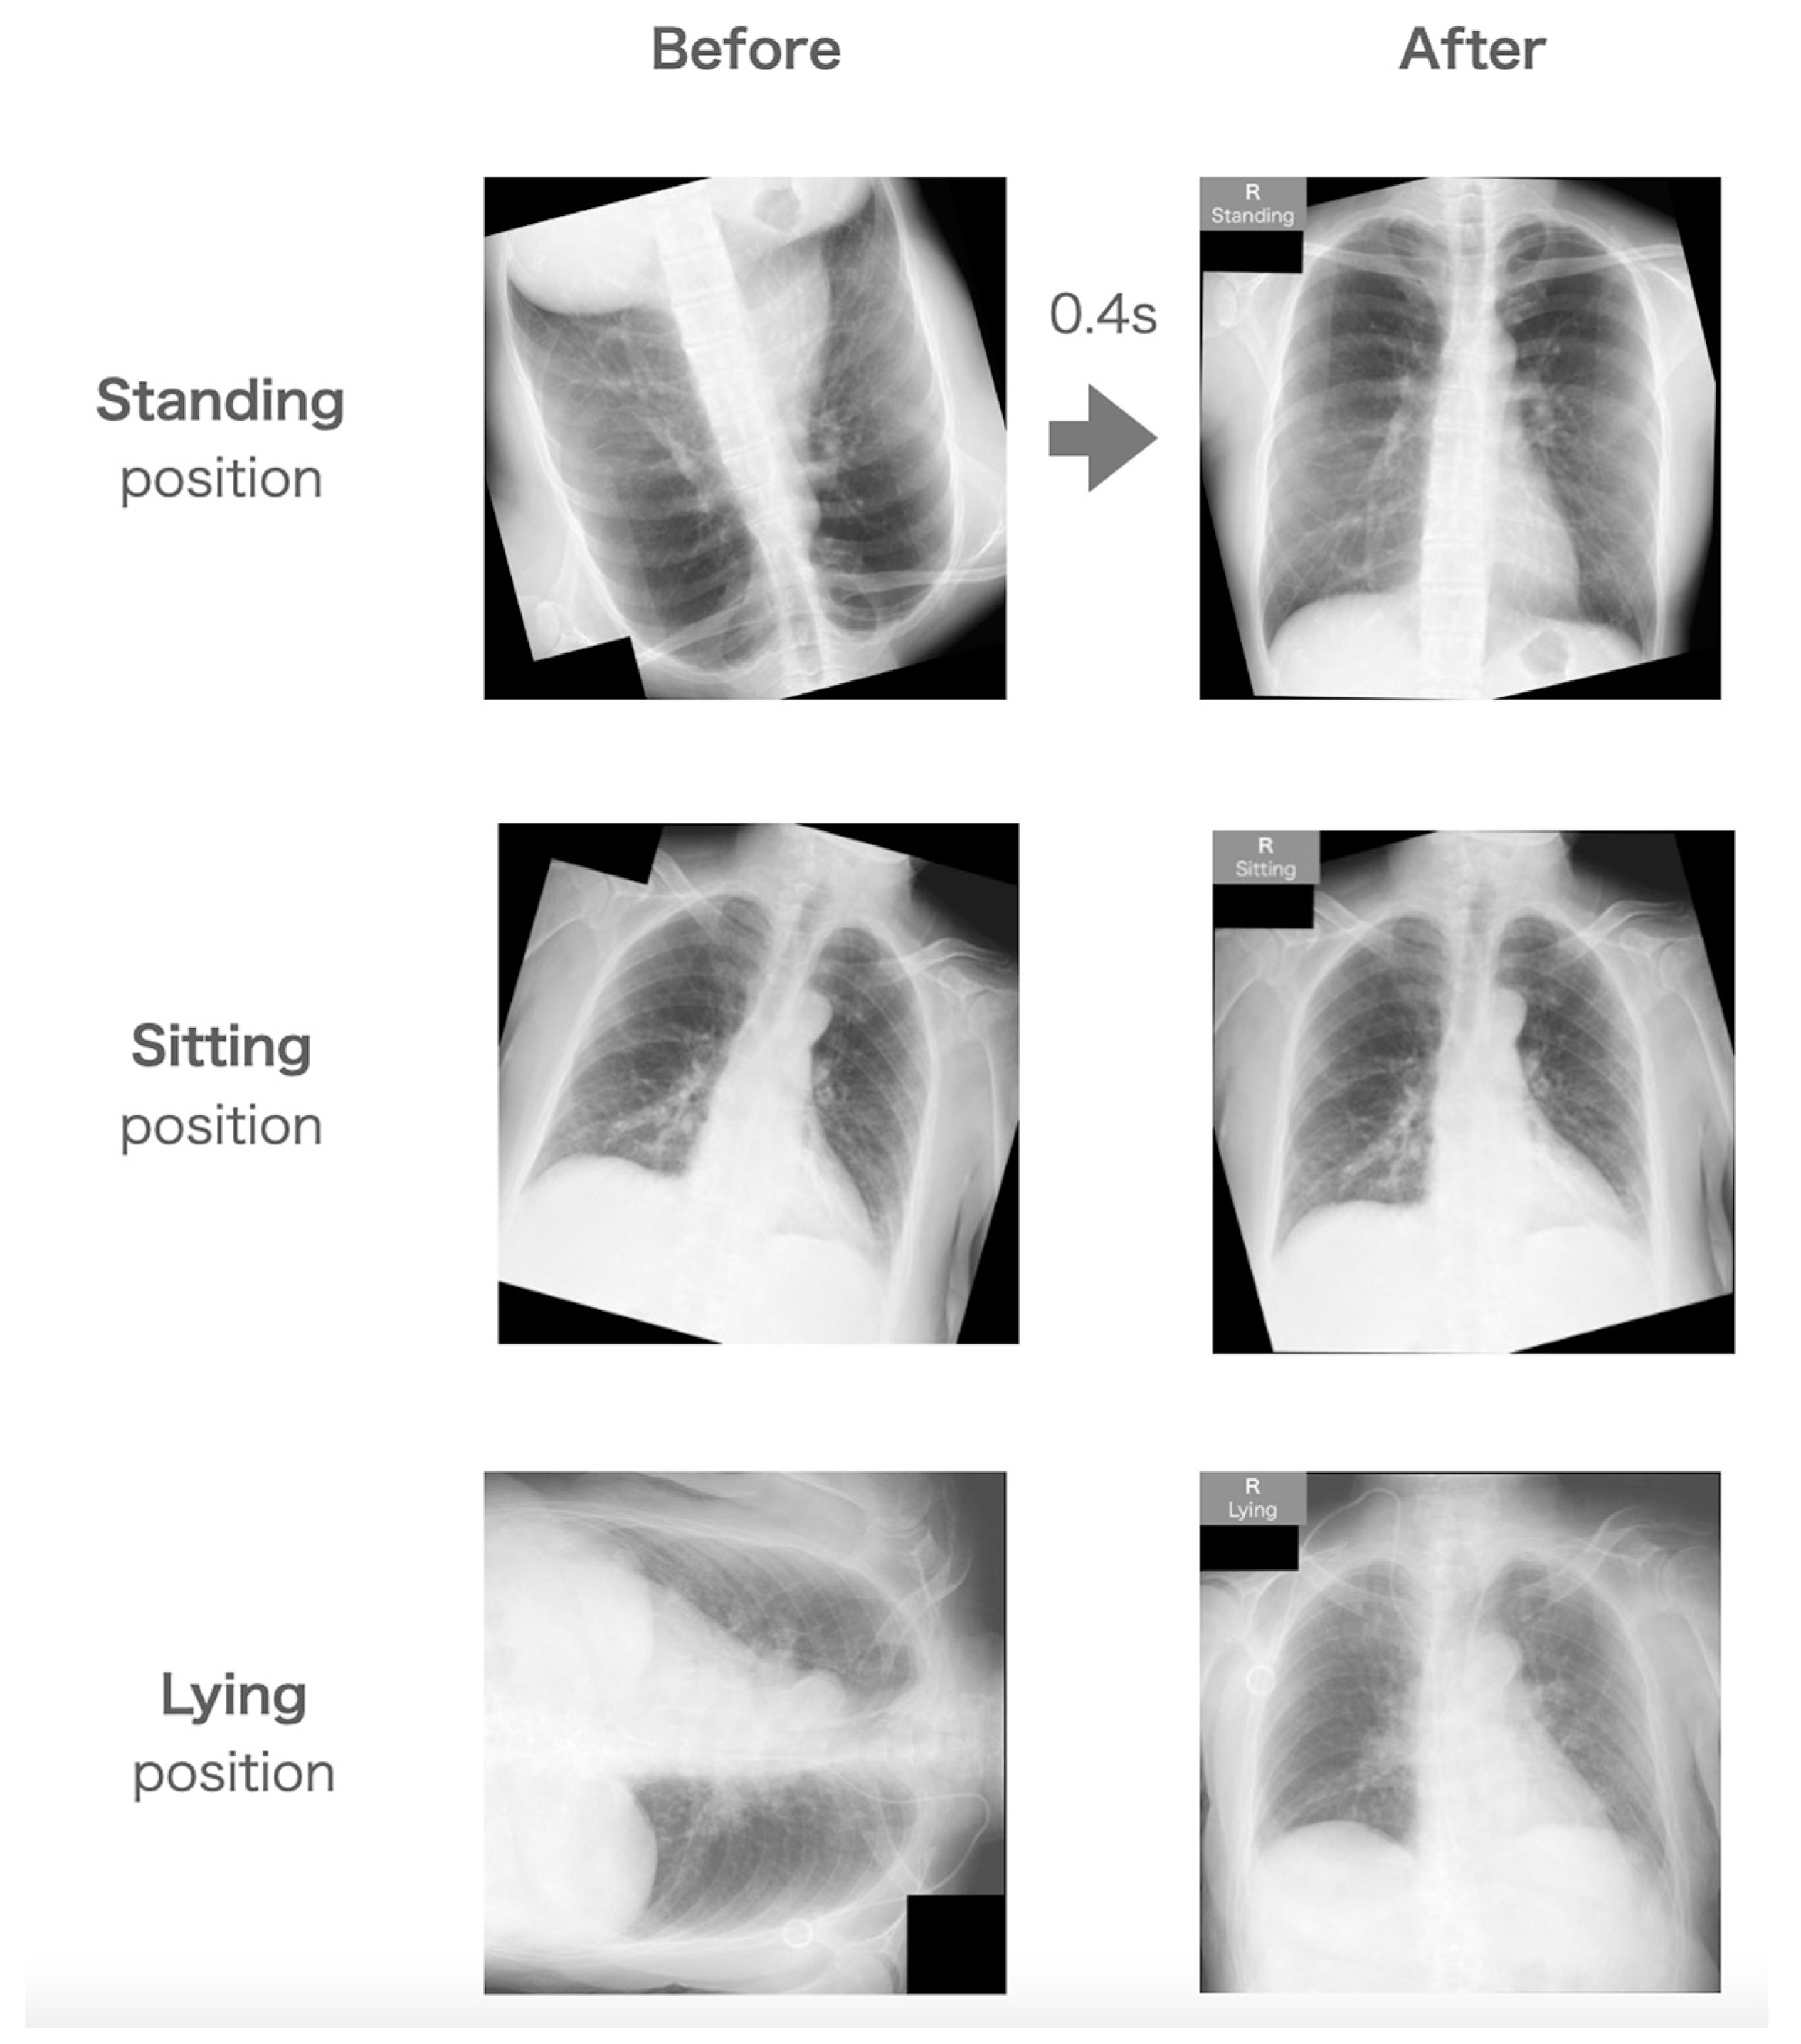

The examples of before–after correction using the QA system are shown in Figure 4. The confusion matrix of the overall test is shown in Figure 5. All images were corrected to normal orientation from various statuses. Makers informing the patient’s position when took CXR were automatically added at right upper corner of images. The overall accuracy was 95.8%, and the time for correction was 0.39 ± 0.074 s. All images with standing positions were completely estimated. A few images were confused between the sitting position and the lying position.

Figure 4.

Images of each patient’s position before and after evaluation through the QA system.

All images were perfectly corrected in their orientation, angle, and left–right reversal.

The patient’s position was estimated with 96% accuracy within 0.4 s.